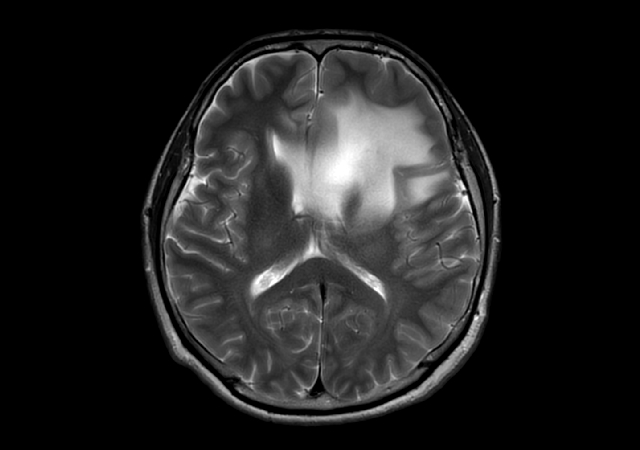

T2w TSE - MultiVane XD